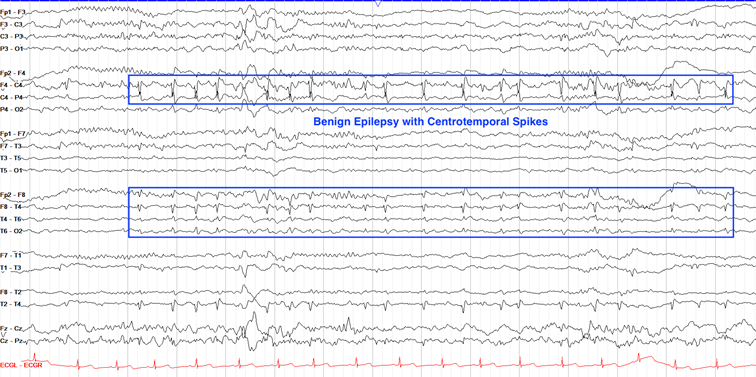

良性Rolandic癫痫(BECTS) | 3–13岁 | 中央颞区棘波,常于睡眠中激活。 |

BECTS